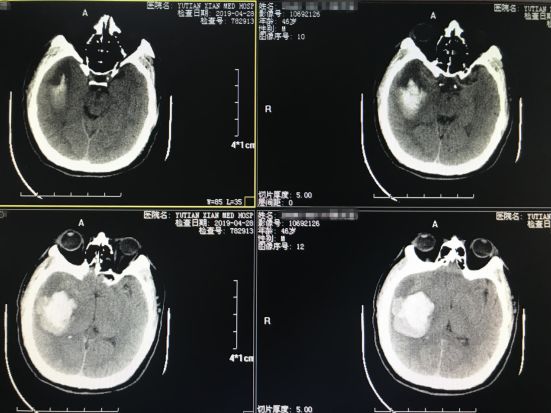

病例一:患者男性,46岁,主因“突发左侧肢体瘫痪、言语不利约1小时”入院,入院后查头颅CT如下:

▉入院时颅脑CT如图所示